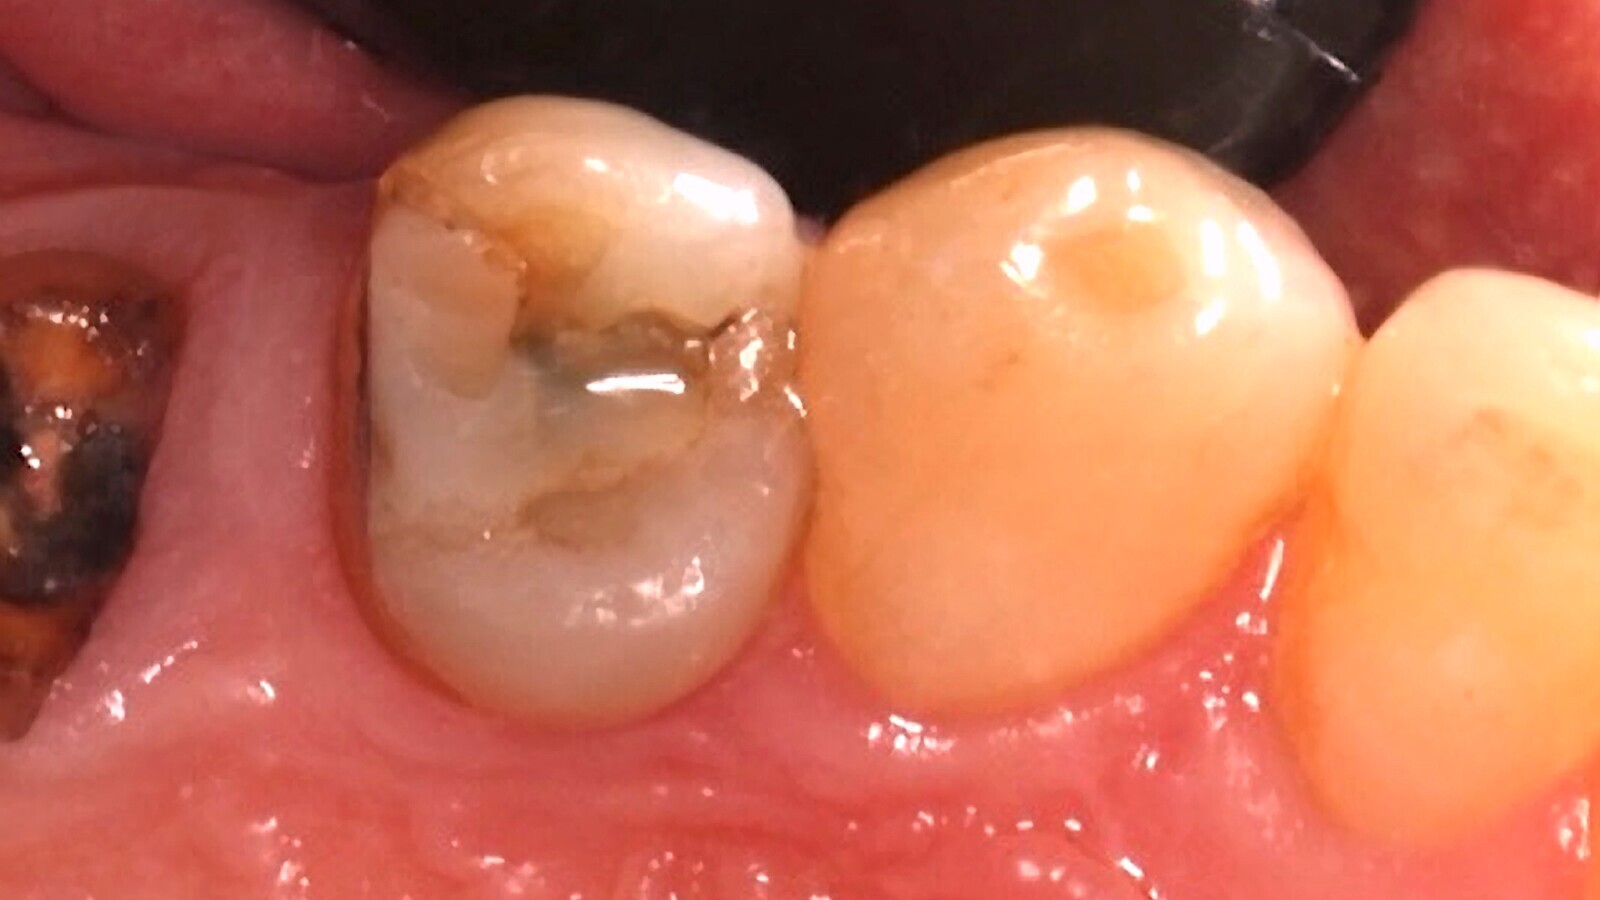

Fig. 1. El diente 46 presenta una sombra subyacente en la dentina apreciada desde oclusal.

Al realizar el examen clínico, el diente 46 presenta una sombra subyacente en la dentina apreciada desde oclusal (Fig. 1), que al manejar el sistema internacional de detección y valoración de caries dental se considera una lesión ICDAS 4 (sombra subyacente en la dentina con esmalte aparentemente intacto). El examen radiográfico, con una exposición de aleta de mordida, evidencia una imagen radiolúcida que alcanza al tercio medio de la dentina (Fig. 2).